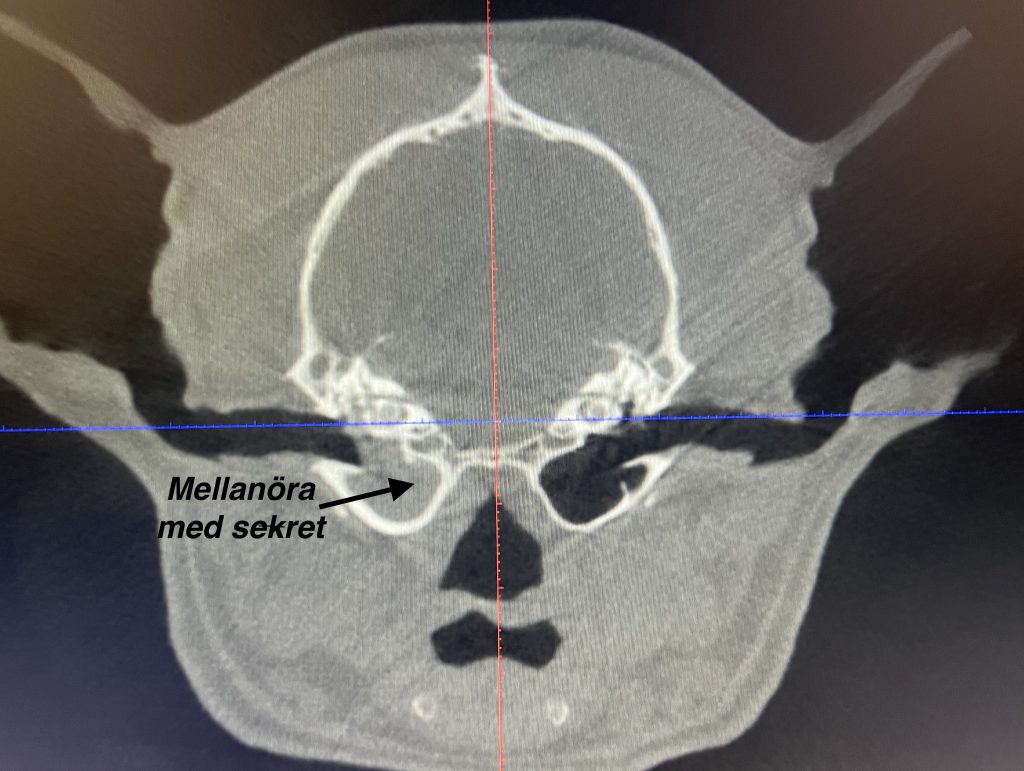

CT-diagnostik för mellanöroninfektion

Vi är så glada för vår CBCT (Planmed VerityVet) som vi haft sedan sensommaren. Vi kan nu på plats erbjuda all diagnostik, utredning och behandling vid kroniska öronproblem på hund och katt. På skiktröntgen ser man om mellanöronen är involverade och till vilken grad. Med videootoskop kan vi sen ta prov från mellanörat och spola […]